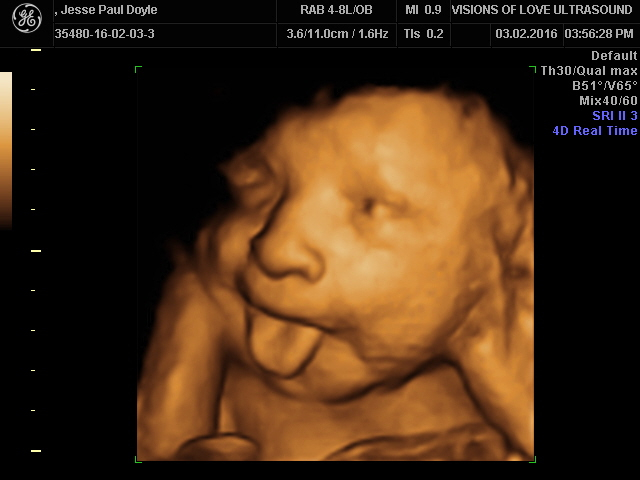

Welcome To The World Of 3d 4d Ultrasound Imaging